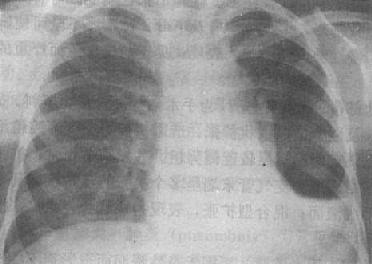

(1)一侧性肺不张:X线现为患侧肺野均匀致密,纵隔向患侧移位,肋间隙变窄(图3-1-7)。健侧肺可有代偿性肺气肿。

图3-1-7 一侧性肺不张

左侧支气管阻塞引起左侧全肺不张,显示左侧肺野均匀致密,

纵隔向患侧移位,肋间隙变窄,膈升高